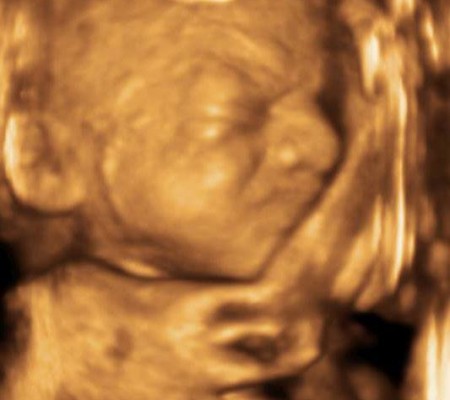

3D i 4D tehnologija omogućava da vidimo površinu bebe na lepši način i pokrete ploda u realnom vremenu.

Takođe nam omogućava da bolje vidimo fetalne mane na licu, šakama i stopalima.

Kao i 2D, 3D i 4D koriste ultrazvučni talas da se kreira slika bebe u materici. 3D je kreirana slika u prostoru dok 4D prikazuje pokret unutar materice pa možemo videti kako se beba smeje, mršti ili zeva.

Da bi se dobile dobre slike poželjno je da se pregled radi između 24 i 32 nedelje trudnoće.